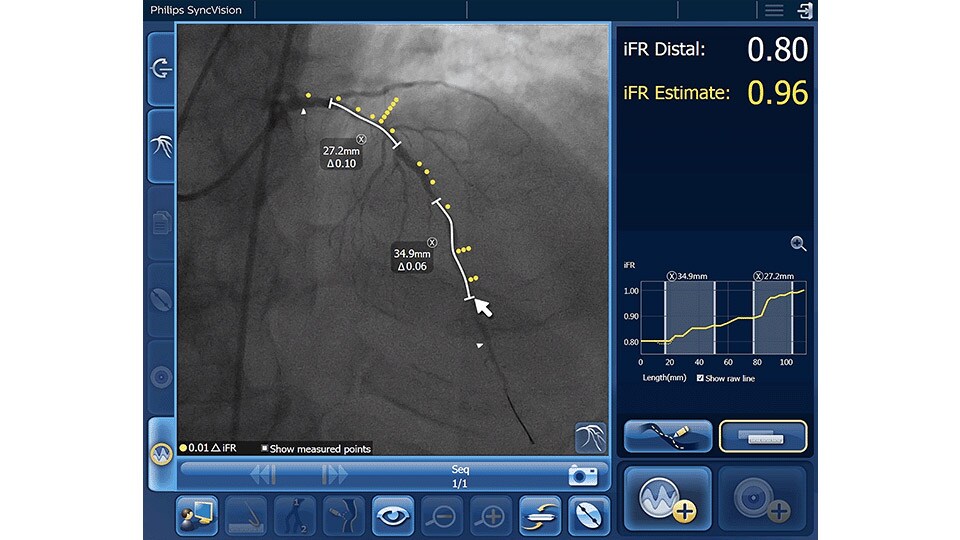

iFR

Only Philips instant-wave free radio (iFR) has co-registration for advanced physiologic guidance, allowing you to precisely determine lesion location and severity.

iFR Co-registration

As an alternative or adjunct to IVUS Co-registration, iFR pullback can be co-registered onto the angiogram to assess both the degree and length of vessel stenosis.